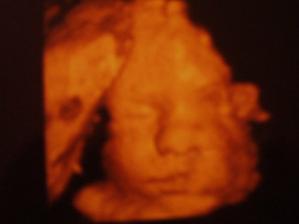

Michálek je už na světě🙂

Míša se nám narodil 7.6.2008 v 15:26, váha 2700g a 49cm, narodil se v porodnici u Milostrdných bratří v Brně.